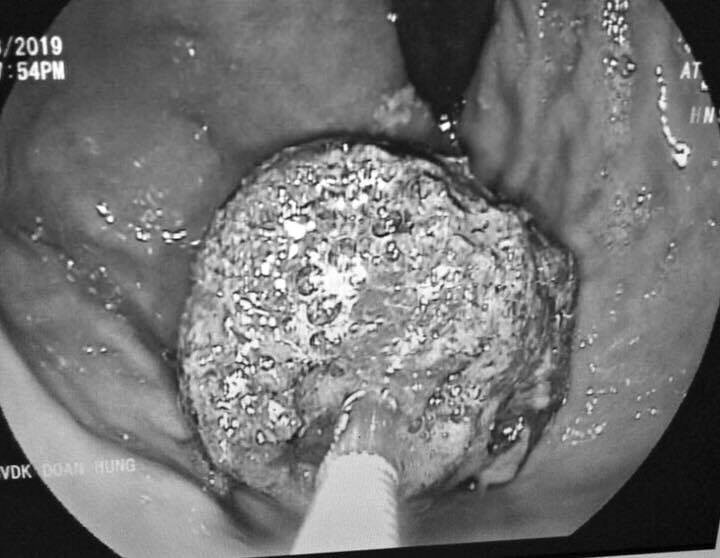

Hình ảnh khối bã thức ăn lớn trong bụng nam thanh niên có thói quen uống trà sữa thay cơm.

Tại đây, kết quả chụp cắt lớp cho thấy, bệnh nhân bị tắc ruột do bã, quai ruột giãn to. Để điều trị, người bệnh được chỉ định phẫu thuật mở ruột, mở dạ dày lấy bã thức ăn.

Quá trình mổ các bác sĩ đã lấy ra 2 khối bã thức ăn lớn trong dạ dày và ruột non bệnh nhân. Hiện tại, tình trạng bệnh nhân dần ổn định và đang tiếp tục theo dõi sức khỏe tại bệnh viện.